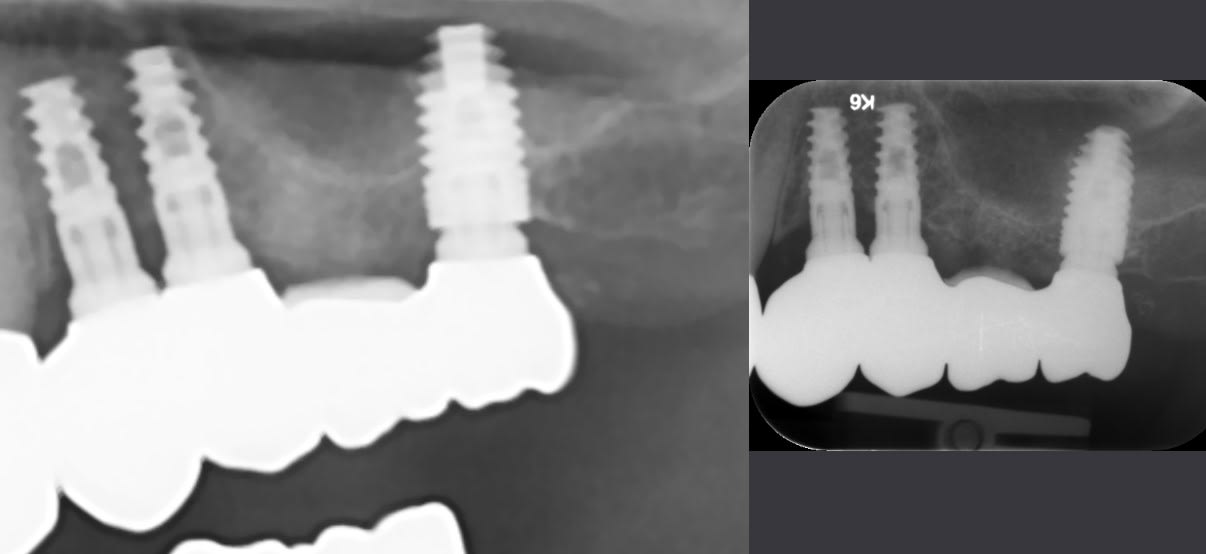

Patiente qui a besoin de la refection d'un bridge 4 élements sur implants 24-25-x-27 transvissé.

Ils ont été posé en 2 temps en espagne en 2017. A mon avis d'abord 24 25 puis 27 avec greffe (peu visible, doit faire peur?).

dommage tes radios sont pas super nettes....

cela dit, les 2 premiers implants sont des implant "spirale" assez classiques avec une connexion interne type "zimmer" en 3.5mm

celui plus au fond m'intrigue plus....car la radio donne peu d'info sur la connexion....mais le profil d'émergence du pilier ressemblant +++ aux deux autres, je dirais même connexion....

donc pour moi, mais sans certitudes à 100% (compte quand même 90%....) je dirais que c'est du Safe implant pour ces 3....

les deux premiers des shark evolution en 3.75mm

le dernier un regular en 4.20mm